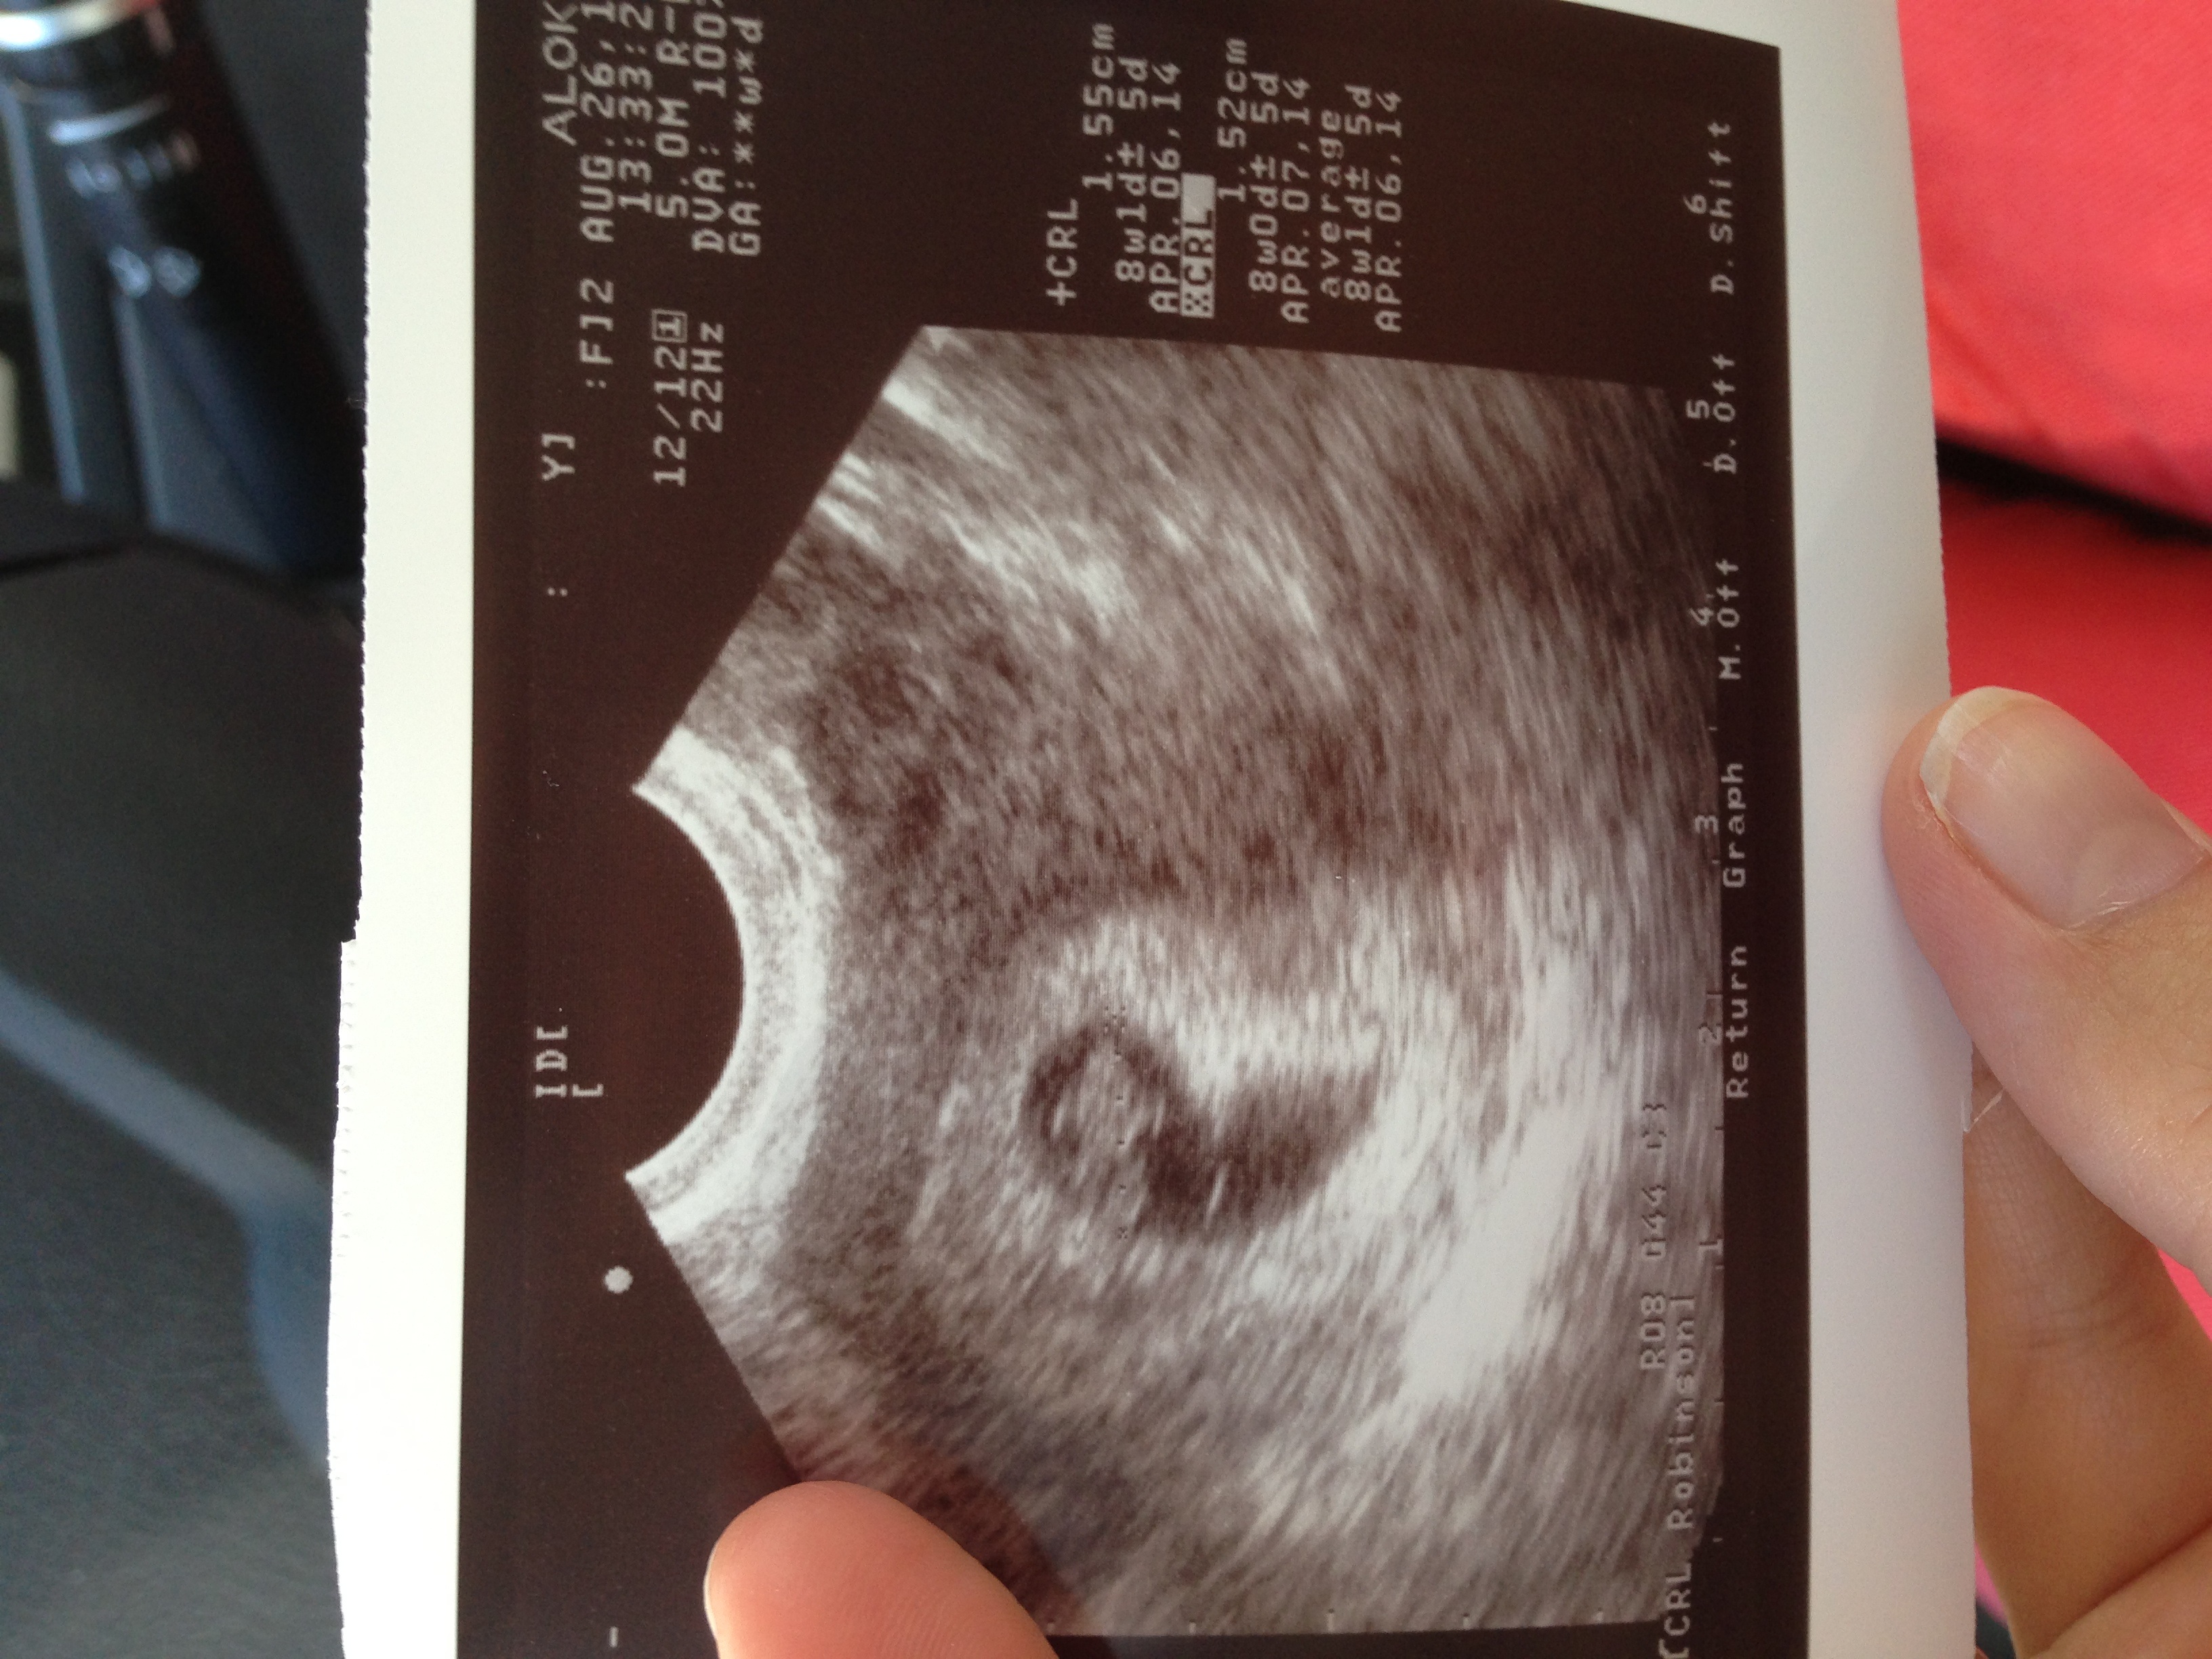

Actually, I think this one looks more like a turtle than a gummy! Everything looked great - keeping my EDD on April Fools. Also got a lot of great info from my OB on how she treats VBACs and feeling a lot more confident about the likelihood of attempting one successfully. Yay.

DD 2/21/2012 & DS 4/1/2014